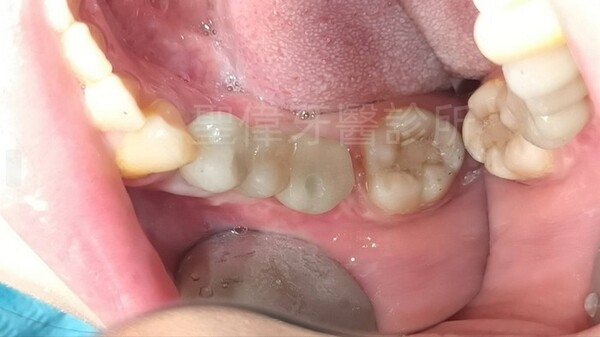

在聖偉牙醫診所植牙效果自然,大推林子揚院長!

終於在聖偉牙醫診所植牙,把缺牙的牙齒補上